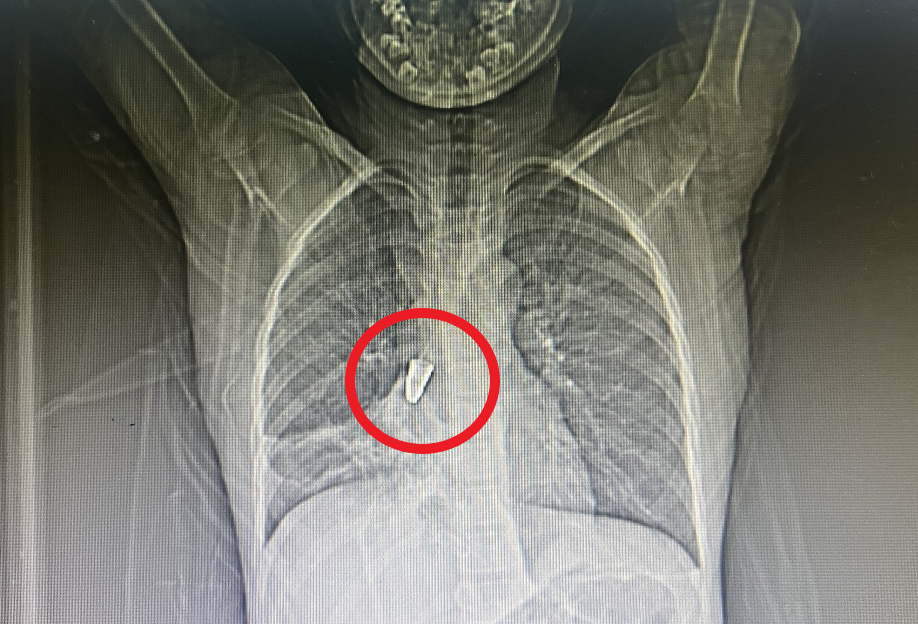

到医院X光片一看

金属笔头终于找到了!

原来笔头戳进了“肺管子”里

笔头和气管卡的严丝合缝,仅剩下2mm小孔维持呼吸道通畅。支气管因受到异物的刺激,不断产生分泌物,唯一的通气小孔随时都可能被堵住。

武汉儿童医院耳鼻咽喉科李栋副主任医师借助支气管镜深入支气管中,在右支气管的深处发现了卡住的金属笔头,笔头呈圆锥状,小头朝下、大头朝上,卡得严丝合缝。